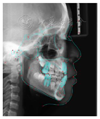

头颅侧位片示:下颌相对颅底位置靠前,趋向Ⅲ类错

,上下切牙舌腭向倾斜,骨龄CS1起始期。

患者治疗前头影测量分析结果

| 北京大学分析法 | ||||

|---|---|---|---|---|

| 测量结果 | 测量值 | 正常值 | 标准差 | 诊断提示 |

| 骨测量 | ||||

| SNA | 84.5° | 82.3 | 3.5 | 上颌相对颅底位置正常 |

| SNB | 81.9° | 77.6 | 2.9 | 下颌相对颅底位置靠前 |

| ANB | 2.6° | 4.7 | 1.4 | 趋向Ⅲ类错![]() |

| FH-NPo | 87.4° | 83.1 | 3 | 颏部前突 |

| NA-Apo | 2.9° | 10.3 | 3.2 | 上颌相对面部后缩 |

| FMA | 28.1° | 31.8 | 4.4 | 均角型 |

| SGn-FH | 62.1° | 65.5 | 2.9 | 聚合生长型,颏部前突 |

| MP-SN- | 32.5° | 35.8 | 3.6 | 下颌提陡度、面部高度适宜 |

| Po-NB | 2mm | 0.2 | 1.3 | 颏部发育量较大,颏部前突 |

| 牙测量 | ||||

| U1-NA | -1.2mm | 3.1 | 1.6 | 上中切牙后缩 |

| U1-NA | 7° | 22.4 | 5.2 | 上中切牙腭向倾斜 |

| L1-NB | 3.5mm | 6 | 1.5 | 下中切牙后缩 |

| L1-NB | 19.4° | 32.7 | 5 | 下中切牙舌向倾斜 |

| U1-L1 | 151.1° | 122 | 6 | 上下前部牙弓突度较小 |

| U1-SN | 91.5° | 104.8 | 5.3 | 下中切牙相对前颅底平面舌向倾斜 |

| IMPA | 85.1° | 94.7 | 5.2 | 下中切牙相对下颌平面舌向倾斜 |